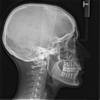

• Au cours du bilan, nous réalisons des empreintes optiques des arcades dentaires et des radiographies des dents et du crâne (et dans certains cas du poignet)

• Ces documents sont ensuite analysés par le Praticien, afin d’établir le plan de traitement.

• Le Praticien vous montre les photographies, les analyses des radiographies et les moulages dentaires et vous explique le traitement envisagé.